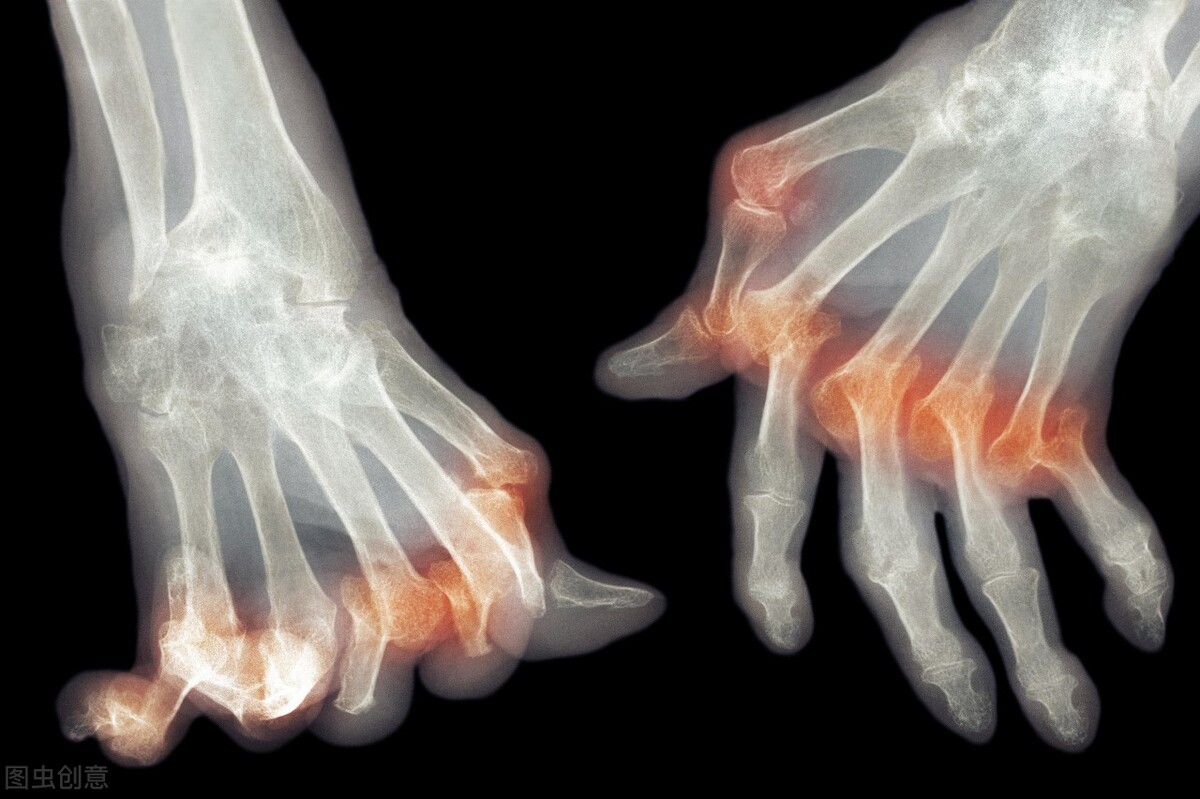

痛风的治疗目前已经成为了困扰大多数痛风患者的难题,这是因为痛风治疗的时候不仅需要讲究用药方法,还需要注意疾病的发作时期。因此在最为痛苦的时候,往往就很难控制患者的病症,让患者头痛不已。其实想要控制好痛风,就需要选择合适的药物来进行治疗,虽然并不存在完全具有针对性的特效药,但是在临床中使用的各种药物,根据患者的情况来进行选择也是较为有用的。